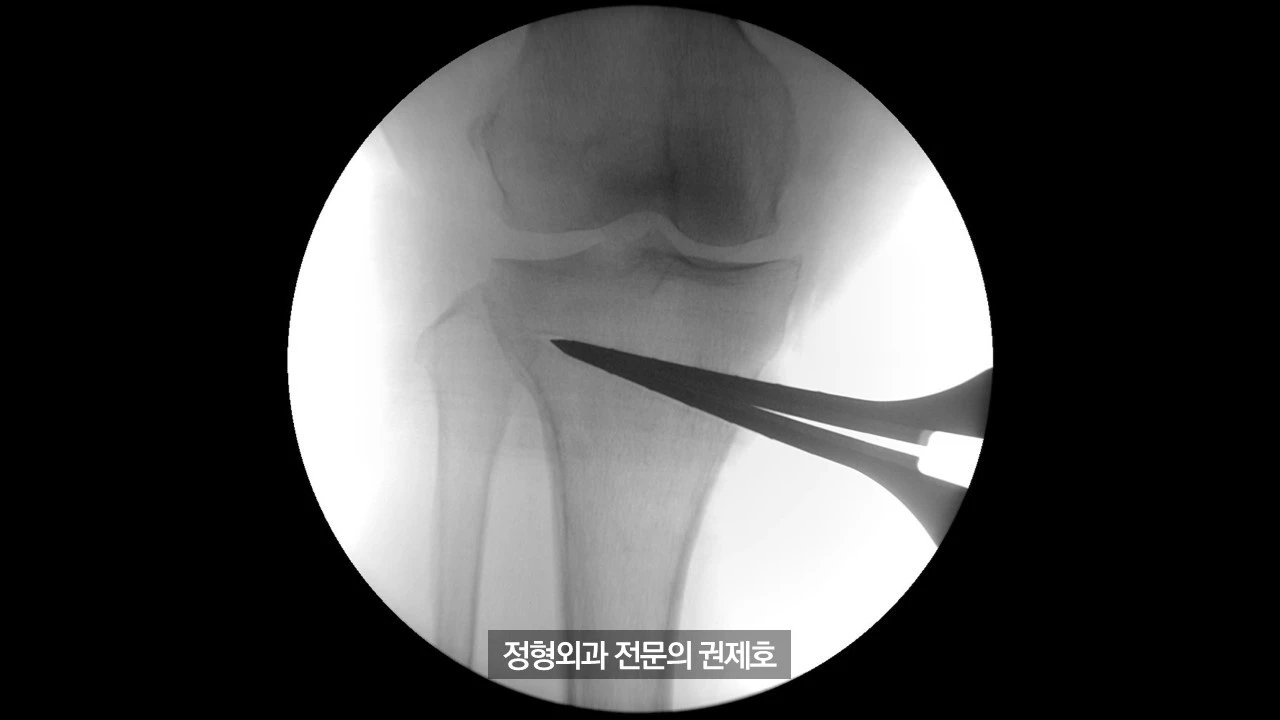

간이 엑스레이 기기를 통해 촬영한 사진이며 (좌측) 가이드 핀을 이용해서 절골할 길을 만드게 되고, (우측) 절골도를 이용하여 천천히 절골을 시행하게 됩니다.